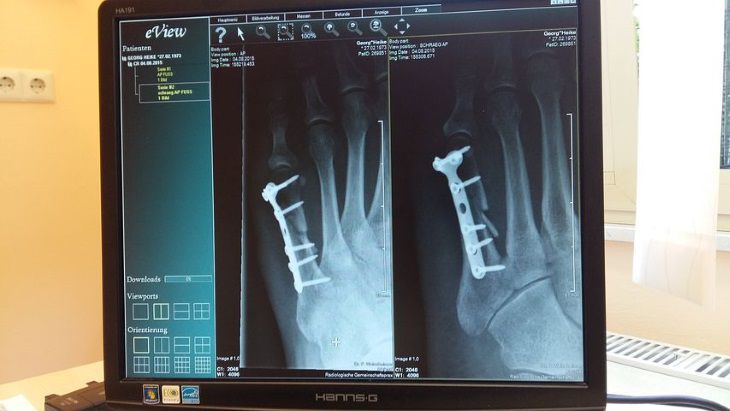

Спираючись на останні результати, вчені рекомендують лікарям не призначати часті рентген-знімки, щоб не підвищувати загрозу розвитку раку, що, як виявилося, цілком ймовірно.